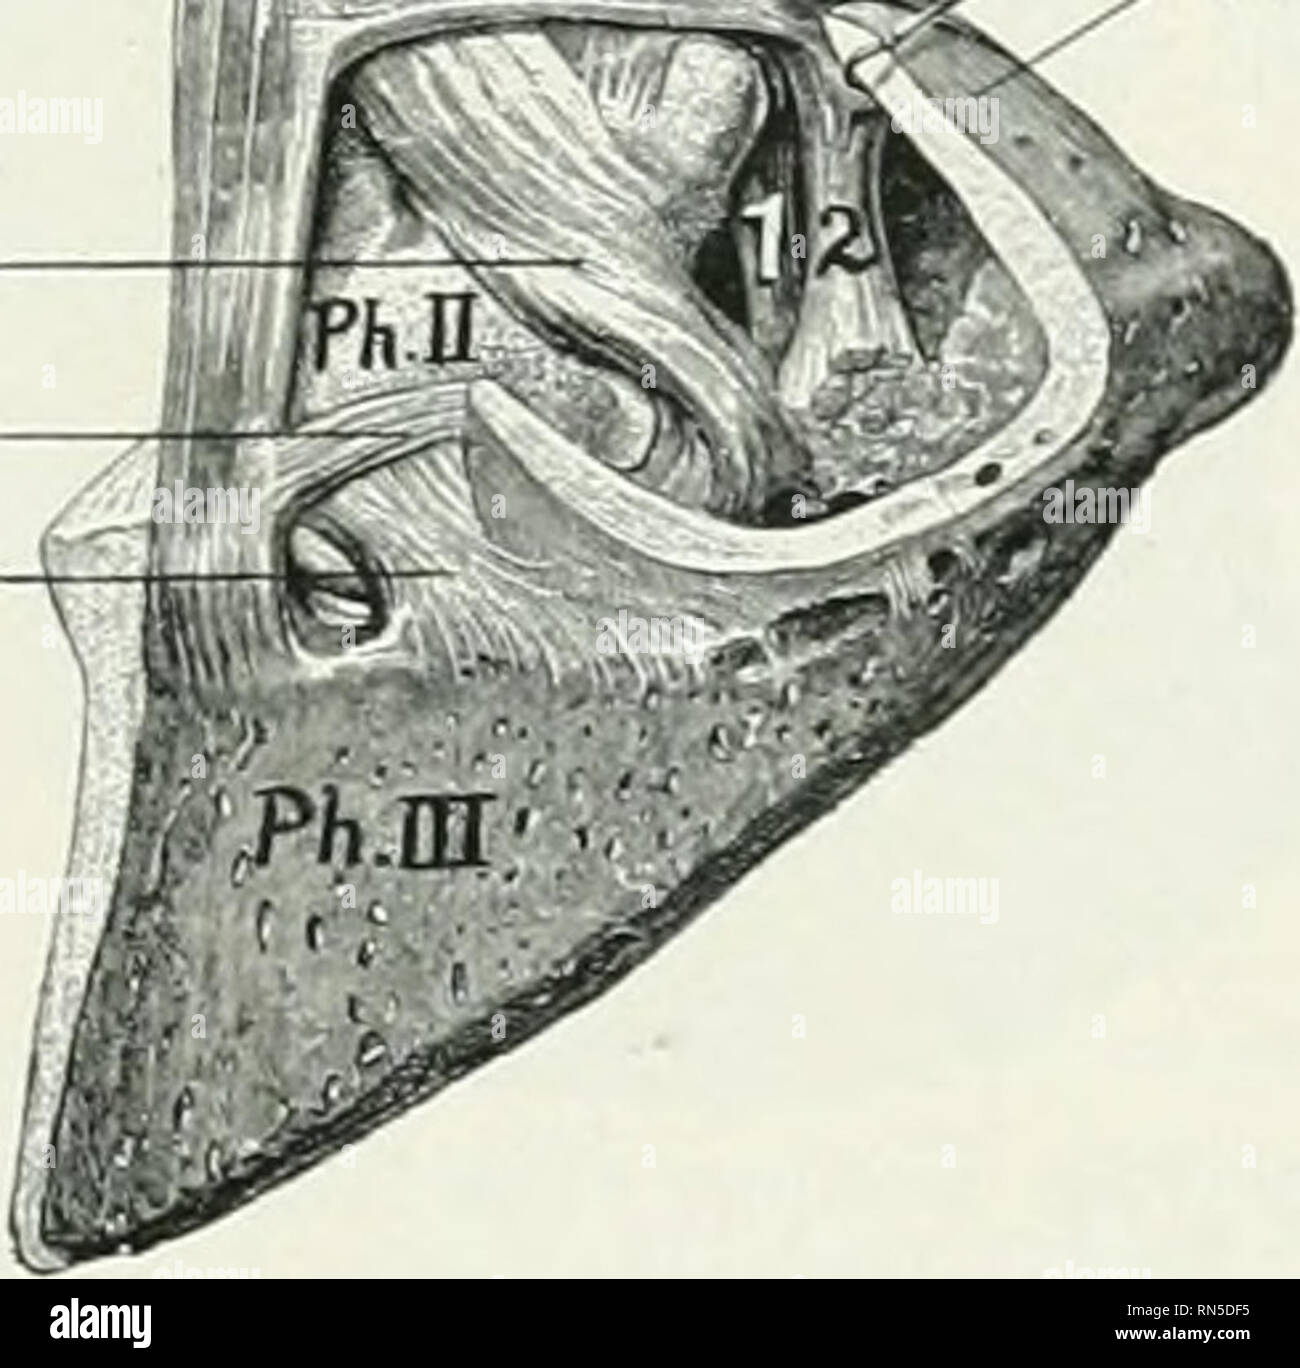

quizlet.comPart 4: Distal Thoracic Limb – Dissection Lab Guide For Ungulate Anatomy

quizlet.comPart 4: Distal Thoracic Limb – Dissection Lab Guide For Ungulate Anatomy

pressbooks.umn.eduAnnular Ligament

pressbooks.umn.eduAnnular Ligament